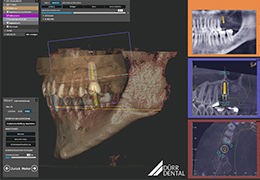

ANYTHINK 经导管主动脉瓣膜置换术分析系统